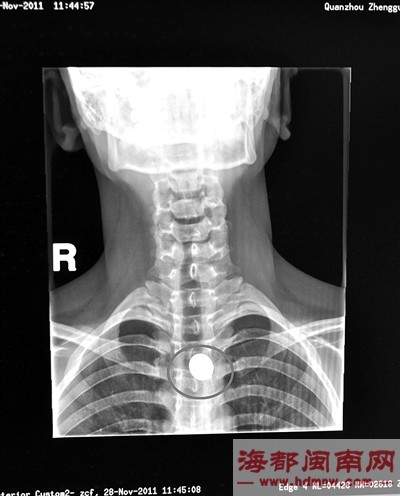

男子送医检查,医生称硬币被卡在食道中(如图),只需待其慢慢排出体外,此外男子嘴角外伤引起吐了口血。